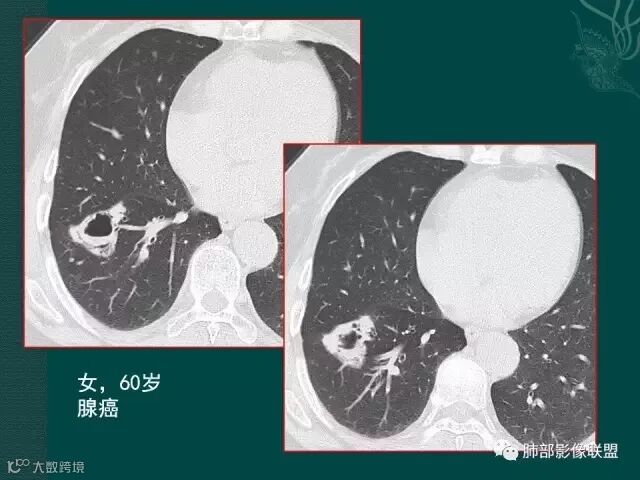

第二个是典型的肺癌坏死后形成的厚壁空洞;

第三个也可以称为空洞,但和第二个不完全相同,壁较薄,内有分隔,我们也称为假性空洞,是支气管活瓣作用形成的,我们也称为假大空。

大片液化坏死,内多发空泡,初学者可能感觉是感染,但红箭头所指洞壁虽然不很厚,但仍可见到边界不清的低密度区,黄箭头所指病变侵犯胸膜。

鳞癌破坏力在所有类型肺癌中,都是最强的,所以出现坏死的几率特别是大片坏死的概率,是远远高于腺癌。

上一个是磨玻璃密度肺癌,边缘清晰,内有分隔,空洞型肺癌伴磨玻璃密度影的,100%为腺癌,很显然这是个假性空洞;

下一个也是肺癌,内有分隔,外下缘箭头所示也是磨玻璃影,这也是腺癌,同时可见叶间裂有转移灶。